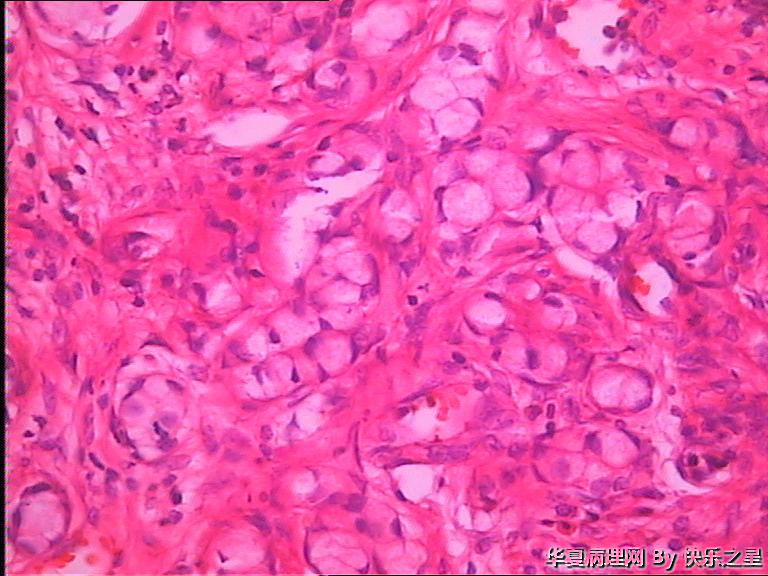

阑尾杯状细胞腺类癌?

男,73岁,因回肠坏死手术,术中切除部分回肠及回盲部,附带 阑尾,长6.5,粗0.7-1.2,表面水中、充血,管腔闭塞,成实性,切面灰白、暗红,质中。

能想到杯状细胞类癌就很不错了!是不是类癌或腺类癌就得看免疫组化了。不怕做不到,就怕想不到。

首选转移性阑尾杯状细胞类癌鉴别印戒细胞癌

应该是类癌,正常腺体不会在肌层内浸润。